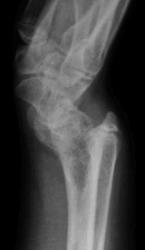

Девочка 14 лет. Ранее за помощью не обращались. Только в этом возрасте родителей и саму пациентку начала беспокоить деформация предплечий.

Рентгенологическая классика для болезни Маделунга:

1. Укорочение лучевой кости.

2. «Скошенность» суставной поверхности дистального эпифиза лучевой кости в ладонную и локтевую сторону, что «симулирует» визуально подвывих костей запястья.

3. «Нависание» полулунной кости над ладонным краем дистального эпифиза лучевой кости.

4. Высота дистального эпифиза по лучевой стороне превосходит его высоту по локтевой стороне.

5. В результате раннего закрытия ростковой зоны по локтевой и ладонной стороне, формируется ладонный и локтевой наклон суставной поверхности.

6. Деформация и изменение расположения проксимального ряда костей запястья, по форме, напоминающей «клин», вершиной которого является полулунная кость.

7. Головка локтевой кости находится в положении «вывиха» и смещена в «тыльном» направлении, по отношению к лучезапястному суставу.